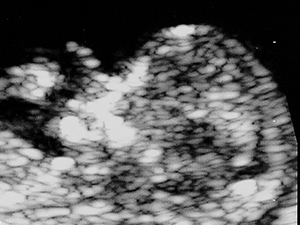

中孕期的胎兒腦部